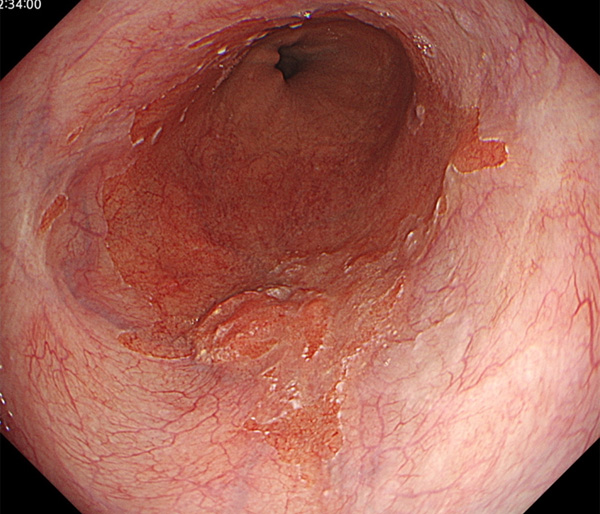

内視鏡所見と病理組織像の1対1対応が可能な症例を公募いたします。主にLSBEに発生した早期癌(HGDを含む)を対象としますが、興味深い症例であればSSBE癌でも結構です。採否は世話人へご一任ください。

症例呈示希望者は応募用紙に記入の上、代表的な内視鏡(2枚)、切除標本(新鮮、固定)、切り出し図、マッピング、代表的組織像とともに、Barrett 食道研究会事務局 barrett.shinshu@gmail.comへお申し込み下さい(10MB以下でお願い致します)。

特に、本邦では極めて稀なlong segment Barrett’s esophagus(LSBE)から発生した早期癌は、診断に難渋する場合も多く、欧米ではランダム生検による検出が標準的とされています。背景のBarrett食道もろとも全体を内視鏡切除+ラジオ波焼灼する欧米と異なり、ESDで内視鏡的な局所切除が基本の本邦では、存在診断+範囲診断(特に水平)を的確に行うことが不可欠です。

そのためには、一流の病理医による組織学的診断とエキスパート内視鏡医による拡大内視鏡像との一対一対応を徹底的に行うことで、『本来、見えないであろう拡大所見の先にある組織構築像が診えてくる』所まで内視鏡診断レベルを上げていく必要があります。その実現には、一対一対応を追究した症例(特にLSBE発生例)1例でも多く経験するしかありません。本研究会でBarrett食道腺癌(LSBE発生早期病変)を共に学び、拡大内視鏡像の一歩先を診るスキルを習得しましょう!一人でも多くの皆様のご参加をお待ちしています。